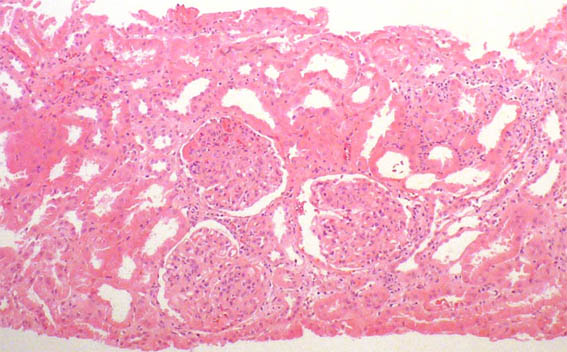

A renal biopsy was done, see the images.

Figure 1. H&E, X100.